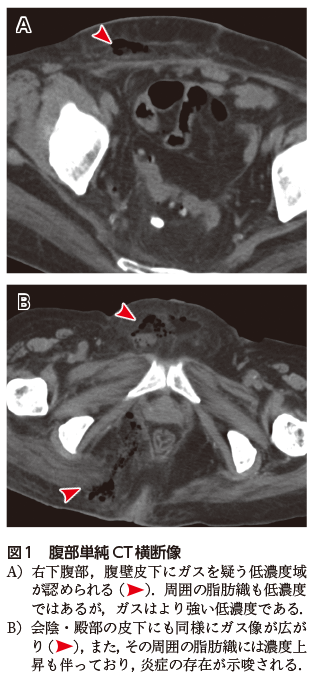

臨床的には,組織壊死に伴う会陰部を中心とした赤黒い腫脹(図2)と悪臭が特徴的である.特に深部での病変の広がりを評価するためにCTが撮影されることが多く,皮下や筋内などのガス像の検出が診断に有効である.造影CTでは大小の膿瘍形成が確認されることも多いが,あくまでもガス像が特徴と考えるとよい.単純CTではしばしば皮下脂肪とガスがともに黒く(低濃度)見えて判別が難しいことがあるが,骨条件などに条件を変えると区別しやすくなる(図3).MRIは軟部組織の炎症の範囲,膿瘍形成の有無など評価するのに有用ではあるが,ガスの検出についてはCTに劣るだろう.

図3